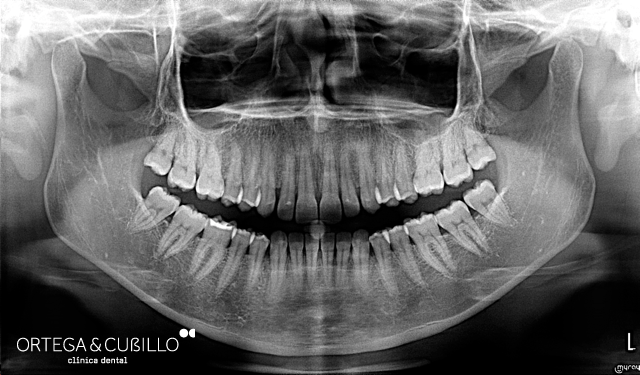

Realizamos ortopantomografías y telerradiografías que son pruebas radiológicas de gran importancia en el tratamiento de ortodoncia e implantología. Asimismo se pueden realizar pequeñas tomografías, radiología de la articulación temporomandibular , senos maxilares y muñeca en este caso para determinar el estado de maduración ósea durante el crecimiento.